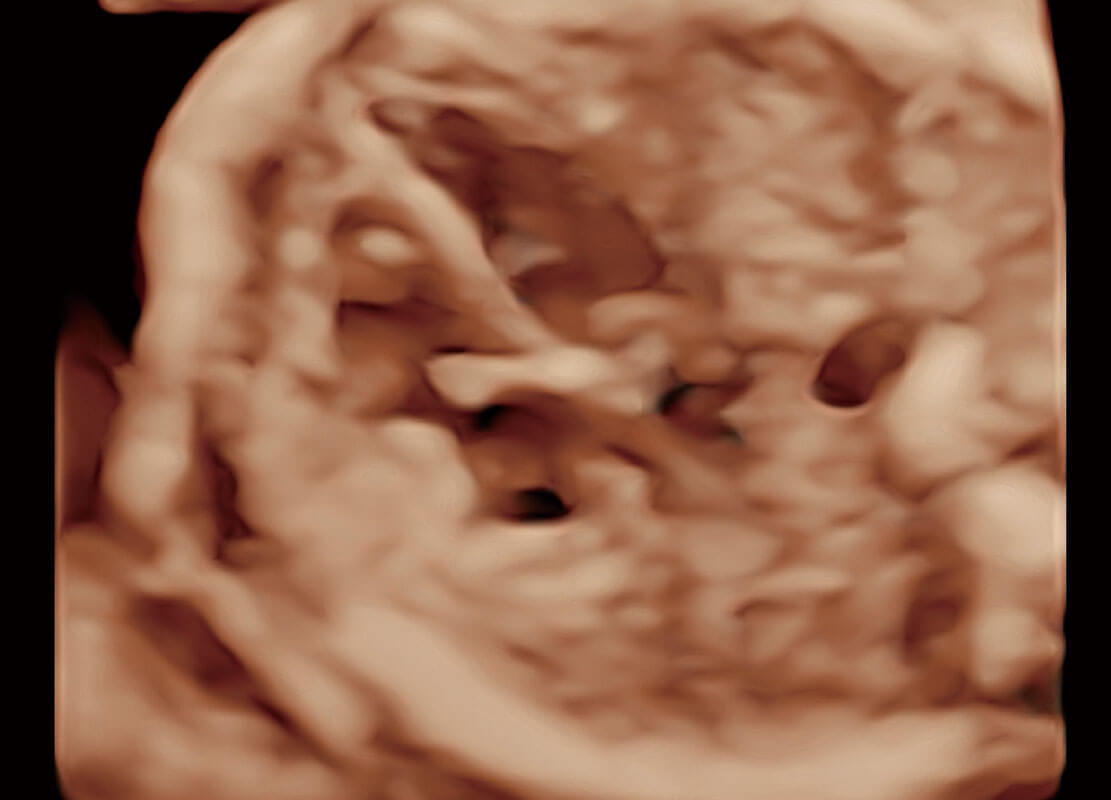

右室双出口

胎心容积成像